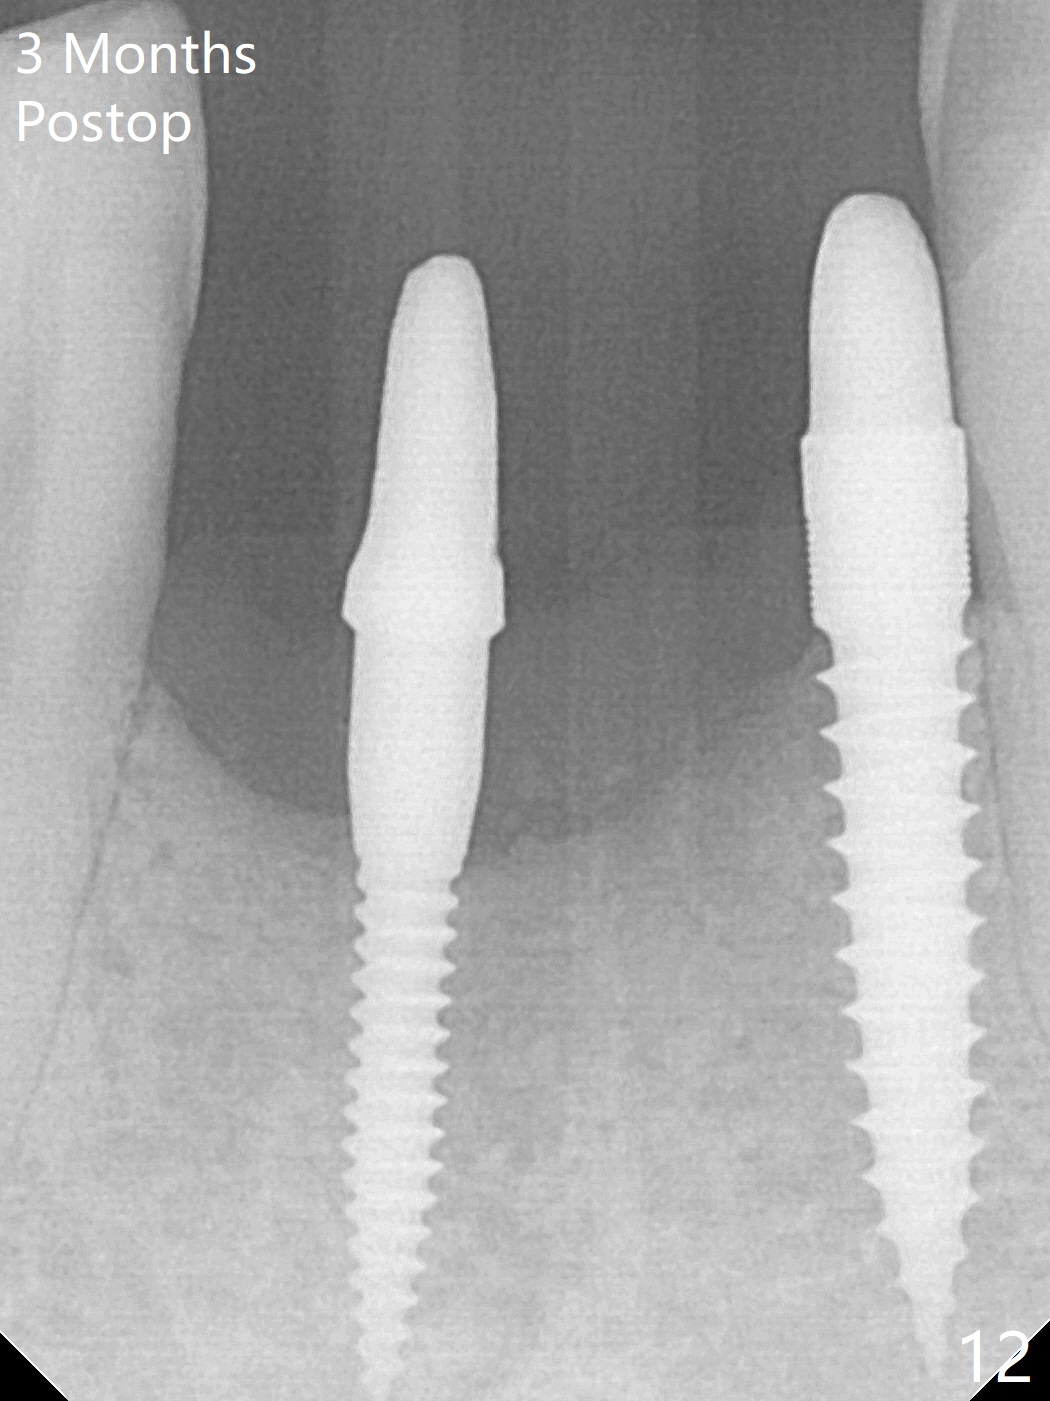

The wound at #25 seems to heal 1 month postop; after prep (Fig.10,11), a provisional FPD is fabricated. Impression is taken for surgical guides of UL and LL implants. The patient requests early final restoration (Fig.12). The small implant placed lingually (Fig.12 *, 2 mm) is associated with the pleasing gingiva in color, as compared to the 3 mm one at #23 with the metal shaded gingiva.